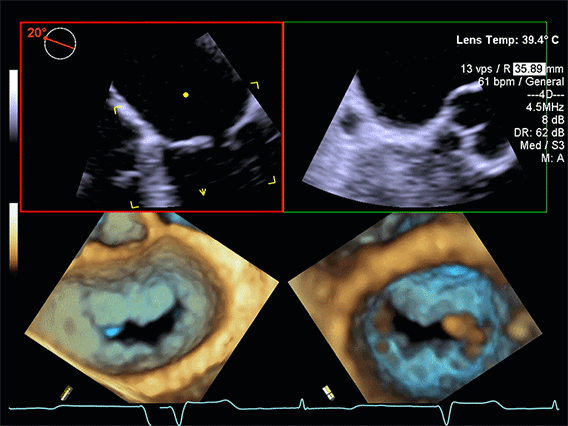

Prikaz kako ACUSON Origin sistem radi

Prikaz rada sofisticiranog AI aparata

Ugrađeni AI moduli u ACUSON Origin sistemu koriste ogromnu bazu ultrazvučnih slika i podataka da bi:

• prepoznali standardne kardiološke prikaze srca i krvnih sudova,

• automatski postavili color Doppler prozor i uzorak za Doppler analizu,

• uradili automatsko konturisanje srčanih šupljina i zalistaka,

• izmjerili parametre poput frakcije izbacivanja, dimenzija komora, brzine protoka kroz zalistke i slično,

• ponudili standardizovan izvještaj koji ljekar dalje dopunjava svojim kliničkim zaključkom.

Ovakav pristup smanjuje varijabilnost između različitih operatera i omogućava da i složeni pregledi budu brži, precizniji i manje podložni ljudskoj grešci.